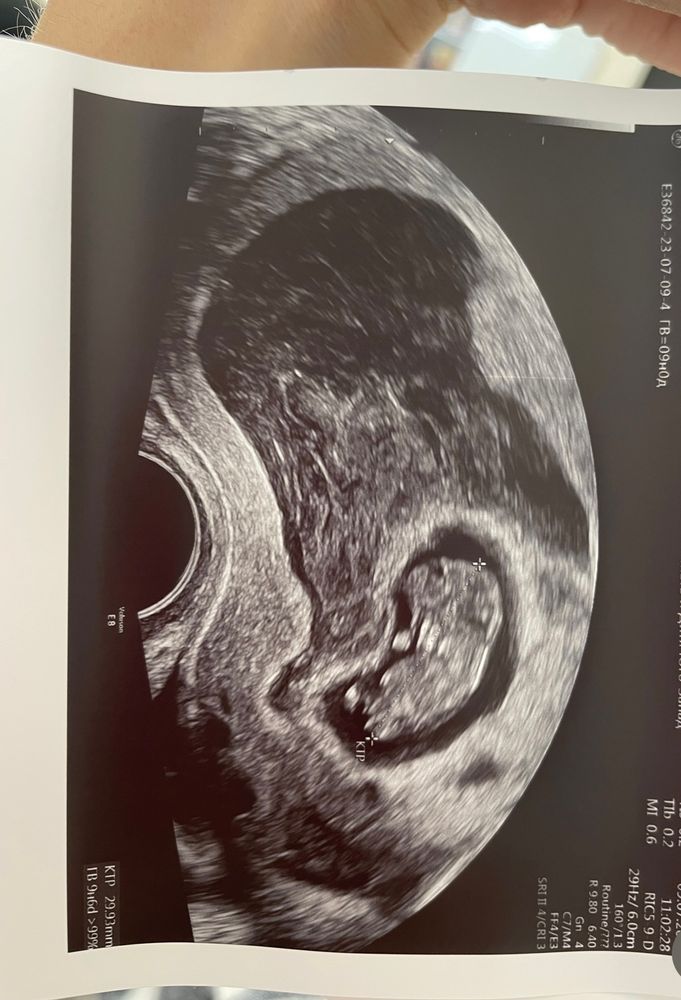

1 скрининг и отслойка. Опять.

УЗИ, КТГ, доплерМалыш развивается по сроку, даже с небольшим опережением. Была отслойка в 6 недель, без выделений. Лежала в стационаре. Прошла без следа. И вот опять. Выделений нет. Как дождаться понедельника. Девочки, у кого были отслойки на таком сроке? Чем все закончилось? Врач сказала к малышу вопросов нет, развитие и кровотоки по нормам. Но на сердце тревога.

Вот огромное черное пятно на весь экран

Такая гематома считается менее опасной. Она меньше самого плода, и составляет 1/3 часть. Не волнуйтесь, если нет кровотечения алой крови, то скорее всего она сама рассосется. Может быть гинеколог выпишет вам прогестерон в поддержку, может быть постельный режим. У меня было две гематомы в 7 недель и в 13-14 уже большая. С кровотечением, и потом долгими выделениями. Закончилось все рождением здорового ребёнка. 😊